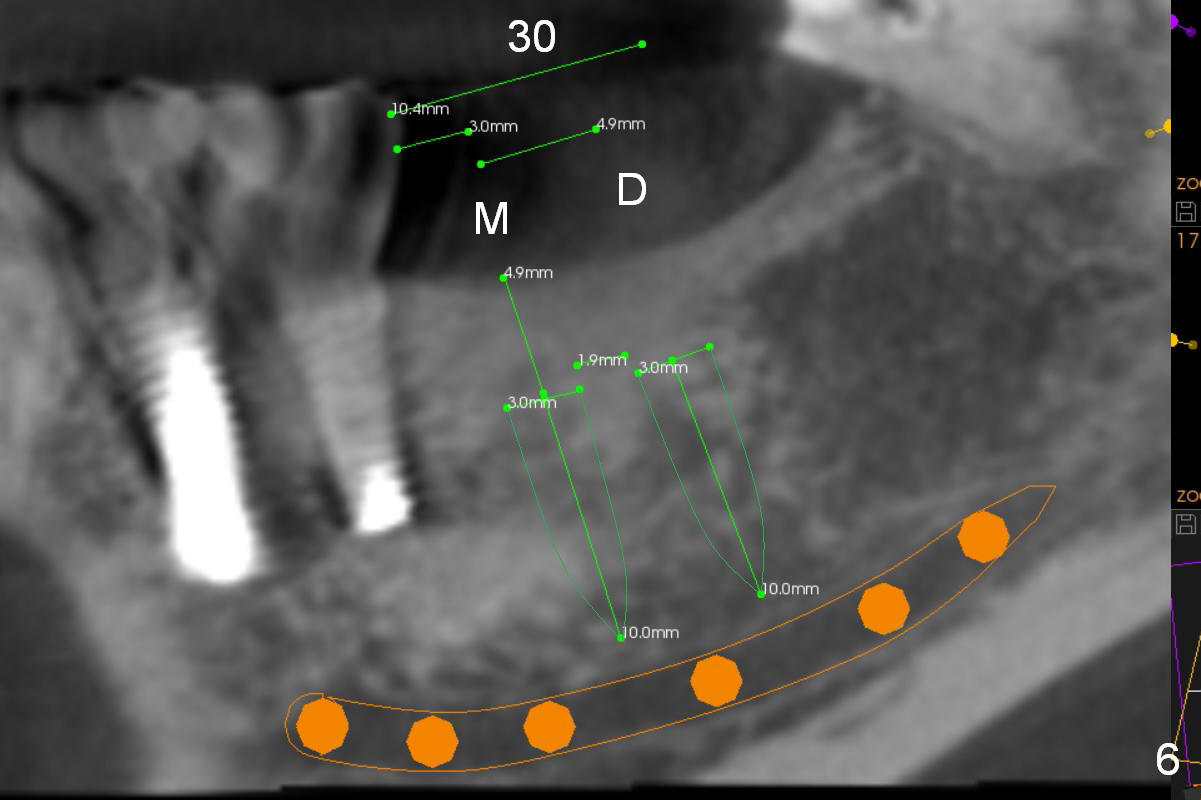

Narrow Ridge at Lower 1st Molar A 56-year-old woman will return for #30 implant placement. The ridge is narrow and pointed at the top. If a 4 mm implant is placed, the ridge has to be reduced for 5.5 mm and the implant will be as short as 9 mm (Fig.1). When 2 of 3 mm 1-piece implants are used, they can be placed higher (Fig.2,3,6). It may be less likely to perforate the buccal plate if 2.5 mm 1-piece implants are placed (Fig.4,5,7). Return to Lower Molar Immediate Implant, IBS Xin Wei, DDS, PhD, MS 1st edition 03/19/2017, last revision 04/03/2018 |